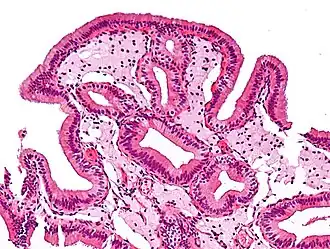

![]() Células espumosas en colesterolosis de la vesícula biliar. | ||

Las células espumosas aparecen en la pared de vasos sanguíneos formando una veta de grasa. Este es el inicio de la formación de la placa de ateromas y son derivadas de macrófagos y células musculares lisas de la pared arterial. En casos de hiperlipidemia crónica, las lipoproteínas conglomeradas dentro de la íntima de los vasos sanguíneos se oxidan por la acción de los radicales libres generados ya sea por los macrófagos, células endoteliales o, especialmente en placas avanzadas, también de células musculares lisas.[1] Los macrófagos digieren las lipoproteínas de baja densidad (LDL) oxidadas por un proceso llamado endocitosis, dirigidos por receptores scavenger, que son distintos de los receptores de LDL. La LDL oxidada se acumula en los macrófagos y otros fagocitos, que luego son conocidas como células espumosas.[2] Estas forman estrías de grasa en las placas de ateroma de la túnica íntima de las arterias.